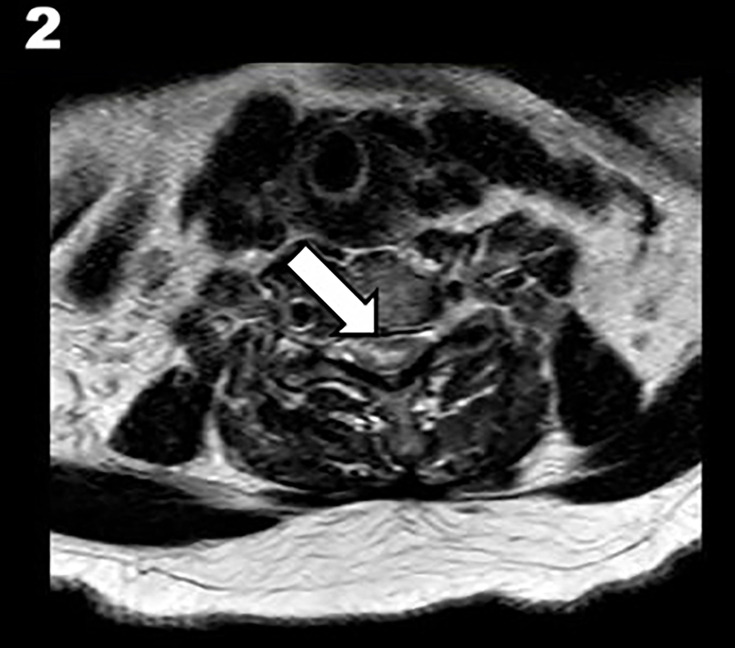

背景:脊髓梗死(SCI)与不良临床预后相关。静脉溶栓(IVT)是一种公认的治疗缺血性脑卒中的方法。然而,其在脊髓损伤中的疗效尚不清楚。目的:我们报告一例急性脊髓缺血溶栓治疗后明显改善的病例,并回顾目前的文献,探讨这种治疗的安全性和可行性。方法:我们回顾了脊髓损伤行静脉注射治疗的文献。我们回顾了他们的病史、临床表现和报告的结果。结果:除了我们的病例,我们的回顾包括19例脊髓损伤的IVT治疗。平均年龄62.87±15.27岁,女性占36%。大多数病例为自发性,并在发病后240分钟内得到治疗。89%的病例取得了良好的结果,包括在延长的时间窗口内治疗的少数病例。两例均无因出血引起的临床恶化。结论:在某些情况下,在适当的检查后,IVT可能被认为是脊髓损伤的治疗方法。大多数病例取得了良好的结果,没有一例因溶栓后出血而出现临床恶化。该方法的安全性和有效性有待进一步研究。

Background: Spinal cord infarction (SCI) is associated with poor clinical outcome. Intravenous thrombolysis (IVT) is a well-established treatment for cerebral ischaemic stroke. However, its efficacy in SCI is unknown.

Objective: We present a case of acute spinal cord ischaemia with significant improvement following thrombolysis and review the current literature to explore the safety and feasibility of this treatment.